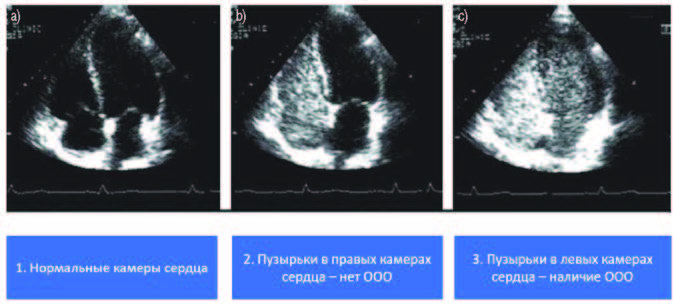

На ЭхоКГ, если нет отверстия между левым и правым предсердиями, пузырьки можно увидеть только в правом предсердие и правом желудочке, так как они будут отфильтрованы в легких и не попадают в левые отделы сердца.

Если имеется открытое овальное окно, то некоторые пузырьки появляются в левом предсердие и левом желудочке.